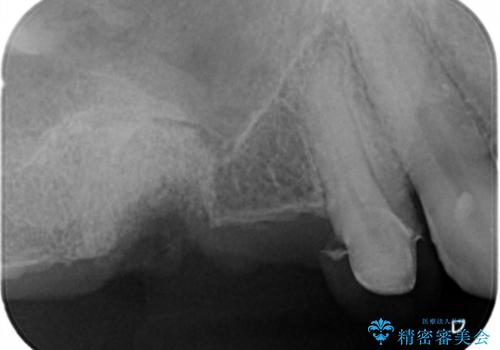

骨の造成を伴う奥歯のインプラント治療

- 破折した歯を放置し、骨が高度に吸収した状態でインプラント治療を希望し来院されました。

インプラントを適切な位置に埋入し仕上げた後にも清掃性を高めるには、必要十分な骨となだらかな歯肉形態の獲得が必要です。

インプラント埋入時に骨の造成を、2次手術時に歯肉の凹みを整え厚みを一定にするような治療を進めていきます。